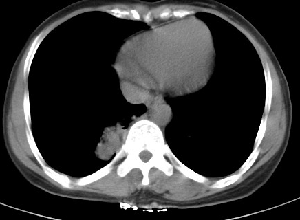

下叶后基底段近膈面见一椭圆形密度均匀增高的阴影,边界较清,其长轴指向内后方,考虑肺隔离症,建议增强扫描了解与主a联系!

右下肺隔离症有可能,另外可能是炎性假瘤

1\\没有什么病史吗,没有看到与腹主动脉有联系呀,肺隔离症不是太象

2\\如果没有明确临床体征,炎性假瘤到是可以考虑

右下肺隔离症考虑,不除外炎性假瘤,建议增强。